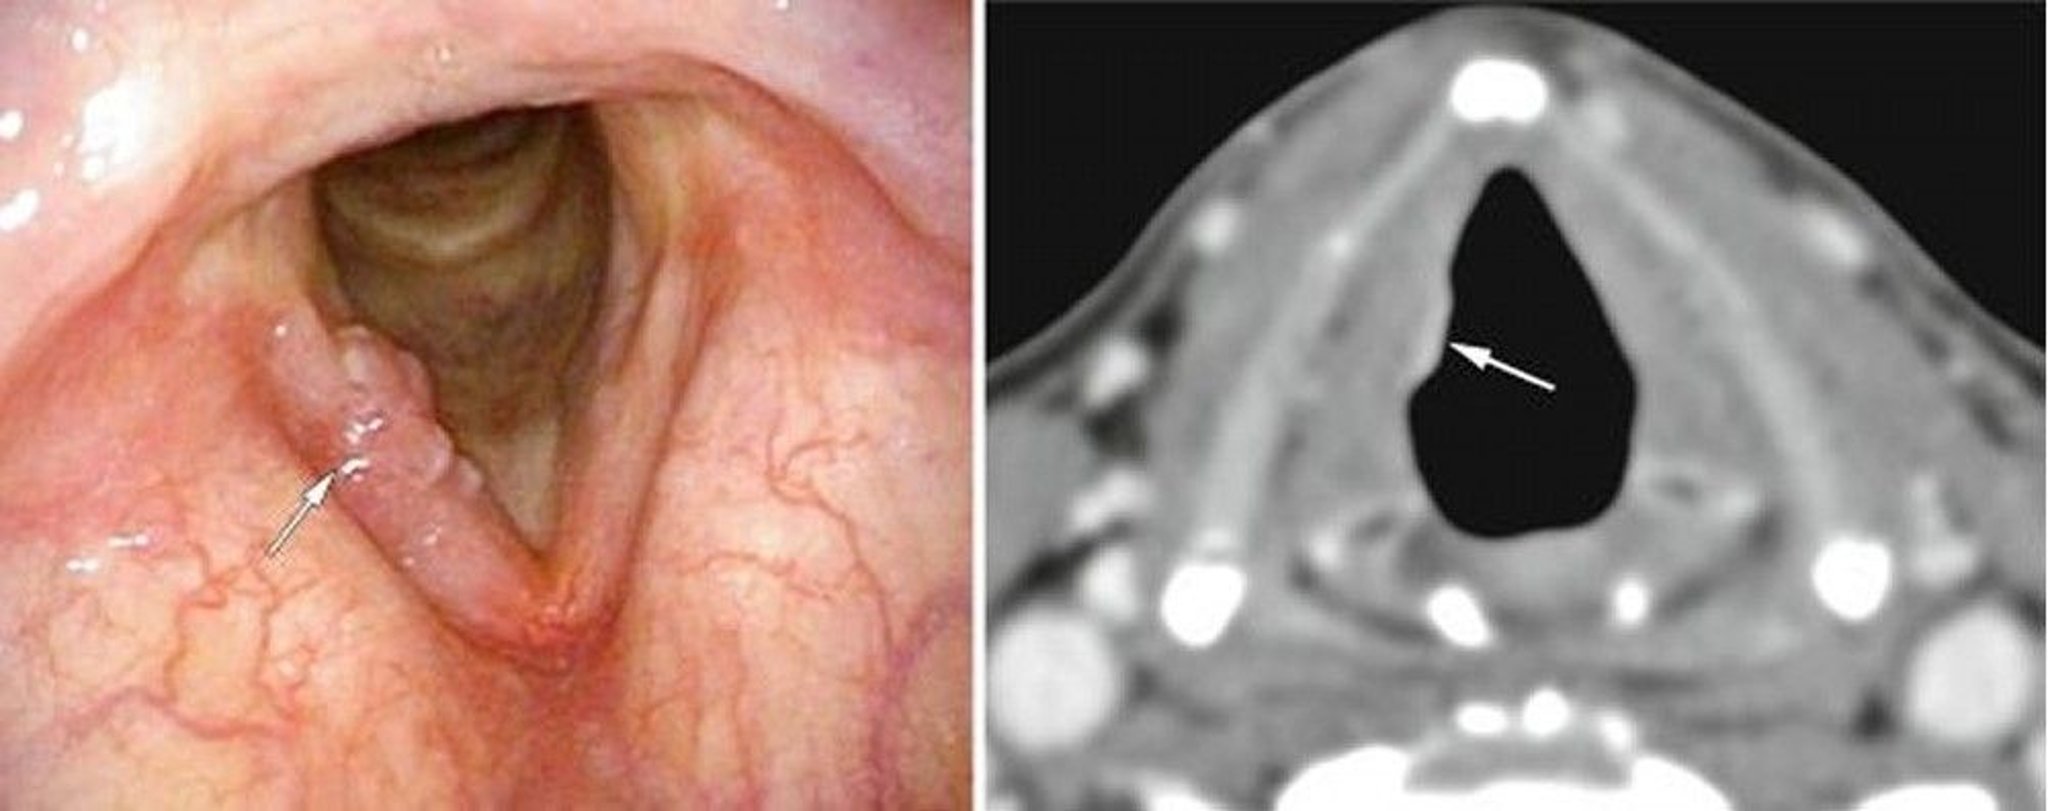

This patient had an early glottic laryngeal cancer, here visible on one vocal cord on endoscopy (left image, white arrow) as excrescences, and on CT (right image, white arrow) as an abnormal soft tissue density.